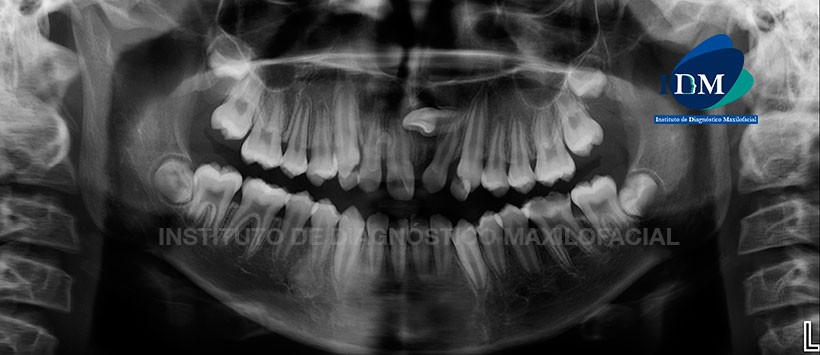

En la radiografía panorámica (Figura 1) se observa presencia de lechos alveolares correspondientes a las piezas 3.2, 3.1 y 4.1 (avulsión dentaria), presencia de alambre de fijación en piezas anterosuperiores con probable fractura coronaria complicada de la pieza 1.1, se evidencia aparente trazo de fractura radicular en el tercio medio radicular de la pieza 2.1.